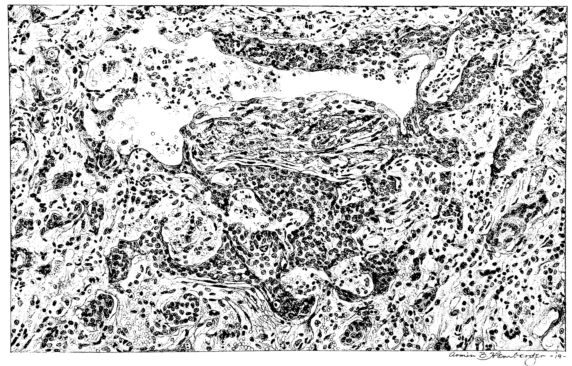

FIG. II. AUTOPSY NO. 98. DRAWING OF A SECTION THROUGH A TRACHEA SHOWING NECROTIZING HEMORRHAGIC INFLAMMATORY PROCESS OF THE MUCOSA.

The changes are less marked, perhaps, in the trachea than in its finer ramifications. The mucosa is constantly more or less destroyed and large areas, usually focal, are entirely devoid of their epithelial covering. This is replaced by a sparse exudate, composed largely of red blood cells, mucus, a small amount of fibrin, and nuclear fragments (Fig. II). It may dip into the submucosa for a short distance, but usually these indentures are associated with the ducts of the mucous glands into which the inflammatory reaction extends. A more striking feature than the exudate, however, is the edema and the congestion of the submucosa. The loose areolar tissue of the submucosa is spread widely apart, and throughout it distended blood vessels are very conspicuous. Occasionally such a vessel is broken and actual hemorrhage appears in the submucosa. Occasionally, too, the inflammation extends down the duct to the mucous gland itself, and here, also, aplastic inflammatory reaction is evident, inasmuch as the acini now stain intensely red with the cells undifferentiated from each other and specked here and there by broken remains of the dead nuclei (Fig. III). After the disease has continued for a short period, even at the end of five or six days, some regeneration of the epithelial lining may be seen (3) (Fig. IV). But despite this, the acute picture persists, and there goes on, side by side, an attempted repair characterized by epithelial regeneration and the same evidence of acute change. Since the lesion is essentially a superficial one, scars or contractures of any extent are not encountered in the trachea, even in examples of the disease that have ended fatally only after many weeks.[4]